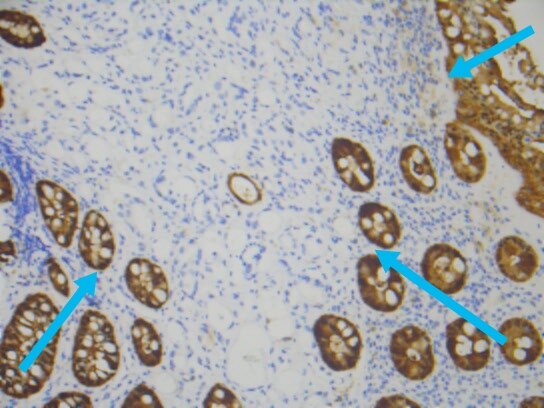

上述免疫组化结果辅助诊断为前列腺腺泡腺癌累及直肠。

加上上述实验室检查,血清psa升高显著,前列腺腺泡腺癌累及直肠就确诊了。所以,老年男性,直肠占位,不能忽视前列腺癌累犯。上述案例,也一再显示癌的发生发展,很长时间内都是静悄悄的,癌可以逃逸人体免疫系统的监控,而疯狂的无序无节制生长,直到破坏了关键器官或组织,才会引起相应的症状。为此,中老年人,规范的健康体检,规范的肿瘤筛查和血清肿瘤标记物的检测,都是十分必要的。当然,我们自己对自己健康的关注才更加重要。了解自己的身体,关注自己的健康,增加健康常识和健康意识都是重要和必需的。